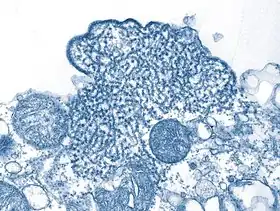

Vírus Nipah (nome científico: Nipah henipavirus)[1] é um vírus transmitido por morcegos. A infecção pelo vírus Nipah pode provocar desde síndromes respiratórias agudas a encefalites mortais.[carece de fontes] Foi detectado pela primeira vez em 1998, durante um surto em Kampung Sungai Nipah, na Península da Malásia,[2] causando 105 mortes.[3][4] Nessa ocasião, os suínos foram os hospedeiros intermediários.[5]